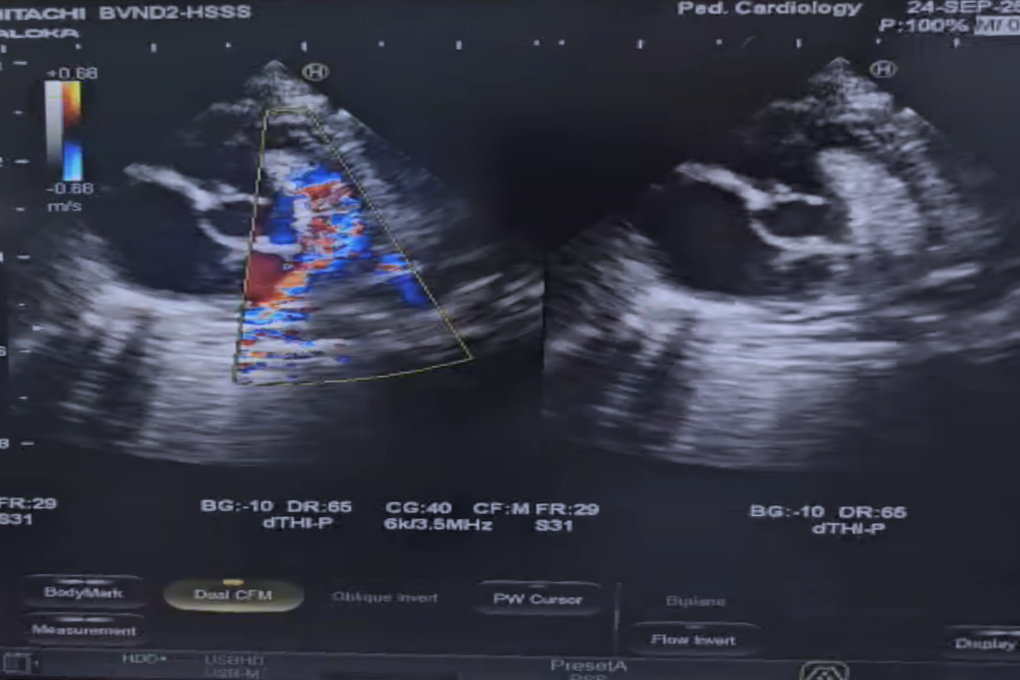

Tứ chứng Fallot là một hội chứng bao gồm 4 tổn thương bẩm sinh ở tim, gồm: hẹp đường ra thất phải, thông liên thất, động mạch chủ lệch sang ngay lỗ thông liên thất và phì đại thất phải. Dị tật này chiếm 5-10% trong tất cả các bệnh tim bẩm sinh.

Theo các bác sĩ, tứ chứng Fallot có thể được chẩn đoán từ trong bào thai, qua siêu âm tim thai. Việc chẩn đoán bệnh từ giai đoạn sớm sẽ giúp trẻ được can thiệp kịp thời ngay sau sinh.